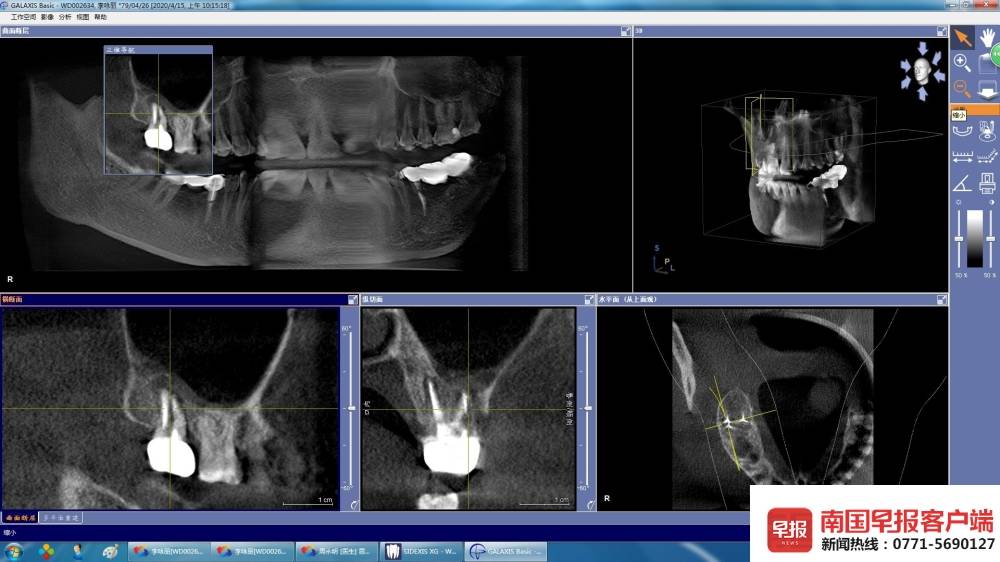

▲拍片显示的牙冠(白色)。

▲拍片显示的牙冠。医院:责任认定需医疗鉴定